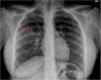

The patient was admitted with a clinical suspicion of erythema multiforme major secondary to M pneumoniae infection. Laboratory tests were as follows: C-reactive protein, 21mg/dL; anti-streptolysin O titer, 222U/mL; white cell count, 22850cells/μL (82.3% neutrophils, with no atypical lymphocytes); M pneumoniae IgM antibody, 292U; herpes simplex virus, Epstein-Barr virus, and cytomegalovirus serology, negative. Chest x-ray showed a pneumonia infiltrate in the right upper lobe (Fig. 2). Skin biopsy revealed an intense vacuolar interface lesion, isolated necrotic keratinocytes, and extensive dermoepidermal separation, with no epithelial necrosis (Fig. 3).